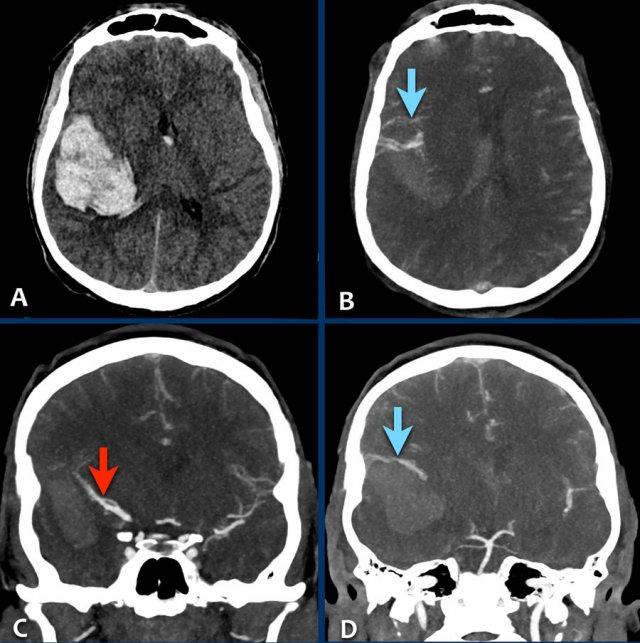

Các hình ảnh thuộc về một bệnh nhân nữ trẻ tuổi với triệu chứng đau đầu khởi phát đột ngột vài giờ sau khi sử dụng cocaine.

Bệnh nhân nhập viện với tình trạng liệt nửa người bên trái.

- A – NCCT cho thấy xuất huyết thùy não ở thùy đỉnh phải với lan rộng vào hệ thống não thất (chấm nhỏ tại lỗ Monroe).

- B – quan sát thấy các tĩnh mạch dẫn lưu lớn.

- C – mũi tên chỉ vào động mạch não giữa phải bị đẩy lên trên do hiệu ứng khối của khối xuất huyết.

- D – quan sát thấy một nidus nhỏ kết nối với các tĩnh mạch bất thường (khá khó nhìn thấy trên CT).